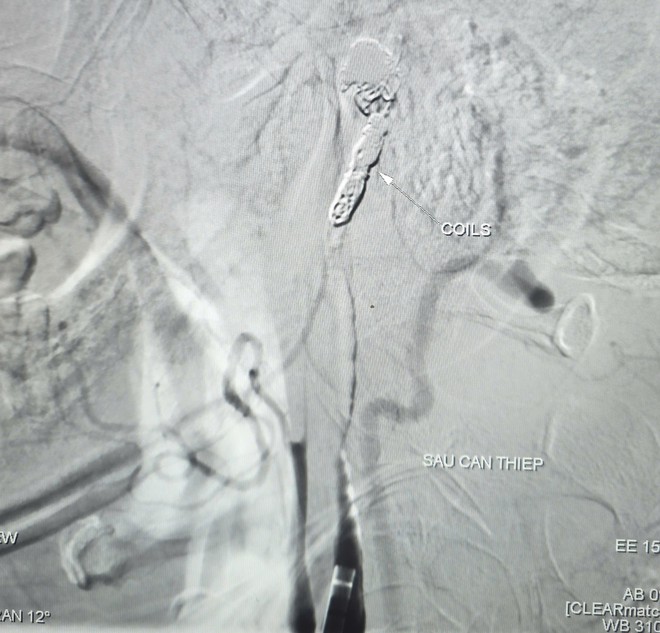

Hình ảnh thoát mạch trước và sau can thiệp. Ảnh: BVCC.

Kết quả chụp mạch ghi nhận ổ giả phình động mạch cảnh trong phải đoạn cổ, dưới nền sọ, kích thước khoảng 4,2 x 4,8 mm, cổ túi phình rộng và đang chảy máu. Ê kíp can thiệp đã sử dụng bóng để kiểm soát dòng chảy, sau đó đưa vi ống thông đến vị trí tổn thương và thả 9 vòng xoắn kim loại (coils) nhằm gây tắc hoàn toàn túi phình và đoạn động mạch cảnh trong phải, qua đó kiểm soát nguồn chảy máu.

Chụp kiểm tra sau can thiệp cho thấy não vẫn được tưới máu nhờ hệ tuần hoàn bàng hệ từ động mạch cảnh trong bên trái qua động mạch thông trước. Toàn bộ thủ thuật được hoàn tất trong khoảng 90 phút. Sau can thiệp, bệnh nhân được theo dõi tích cực. Đến ngày 6/3, người bệnh tỉnh táo, tiếp xúc tốt, niêm mạc hồng, không ghi nhận yếu liệt tay chân, sức khỏe phục hồi ổn định.